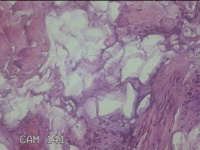

右侧颜面部结节

性别

男

年龄

49岁

临床诊断

皮脂腺囊肿

一般病史

发现右侧颜面部结节5年余。

标本名称

大体所见

灰白暗红色组织1x0.7x0.3cm一块,表面带梭形皮肤1x0.5cm,皮下见结节0.9x0.7x0.3cm一个,切开结节呈实性,切面灰白暗红色,质中。

图1